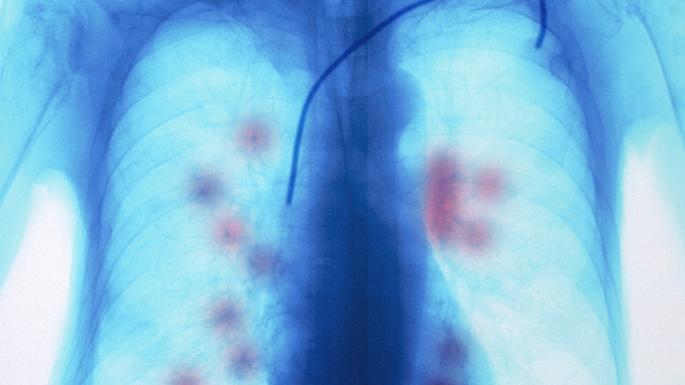

The Irish Cancer Society has said that recent research by the National Cancer Registry of Ireland (NCRI) has shown that lung cancer incidence could double by 2045, with the possibility of substantial increases in the numbers of women being diagnosed with the disease.

As the Irish Cancer Society launches its annual lung cancer awareness campaign, supported by AstraZeneca, Aoife McNamara, Information Development Manager said, “over 2,500 people are diagnosed with lung cancer every year and it is very alarming that these numbers are projected to double over the coming decades.”

The lung cancer numbers, set out in the NCRI Annual Report, suggest that going by population changes alone, cases could double in numbers. However, if increases in female rates and decreases in male rates continue, female cases may substantially outnumber male cases in coming decades with projections showing a 176% increase for female cases.

Ms McNamara continued, “In order to address this increase, we must concentrate now more than ever on detecting lung cancer early. When lung cancer is diagnosed at stage I or II, two-thirds of patients survive at least a year compared with just one-quarter who are diagnosed with a later stage lung cancer. When lung cancer is diagnosed late, treatment options are limited, and survival rates remain very low.

“As was set out in the National Cancer Strategy, we must work towards increasing the numbers of people diagnosed early while also developing a specific awareness campaign for lung cancer. I am delighted to announce that the Irish Cancer Society, supported by AstraZeneca, is bringing the MEGA lungs exhibit to Ireland as part of our lung cancer awareness campaign. The MEGA lungs is a pair of giant inflatable lungs which will be coming to Dublin in January and will encourage people to learn more about their lungs and lung health.”